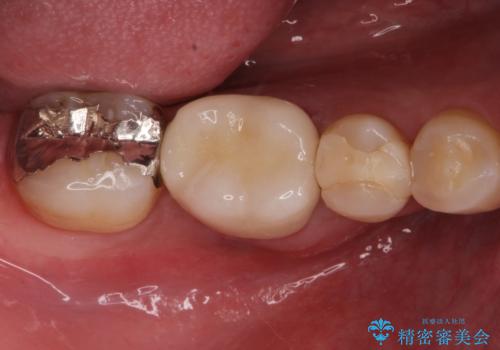

汚れの溜まりやすい銀歯を精度の高いセラミック治療で改善